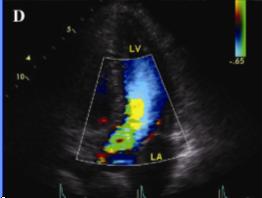

2.肥厚型心肌病

可見不對稱性室間隔肥厚,室間隔厚度與左室後壁厚度之比大於1.3:1;二尖瓣前葉收縮期前移;左心室腔縮小,流出道狹窄;左心室舒張功能障礙,包括順應性降低,快速充盈時間延長,等容時間延長等。